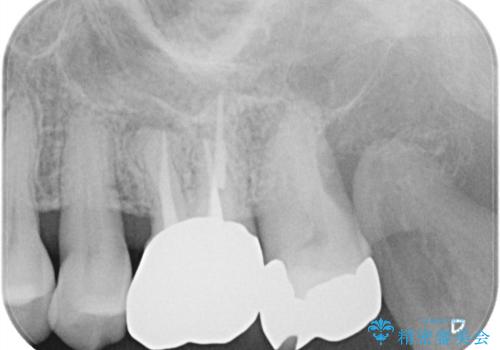

【根管治療】ズーンと痛い歯の治療。

- 奥歯付近がジーンと痛いことを主訴に来院されました。

左上7番の歯は、歯髄検査にて反応を示し、歯周ポケットはありませんでした。

親知らず抜歯を行い、痛みの変化や歯根吸収の有無を確認したのち、抜髄処置を行っています。

症状改善し、遠心の骨の回復も認めます。

バイオセラミックシーラーを使用して根管充填を行っています。